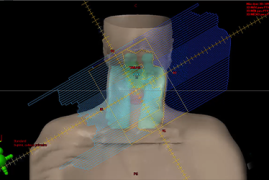

Radioterapia Conformacional 3D